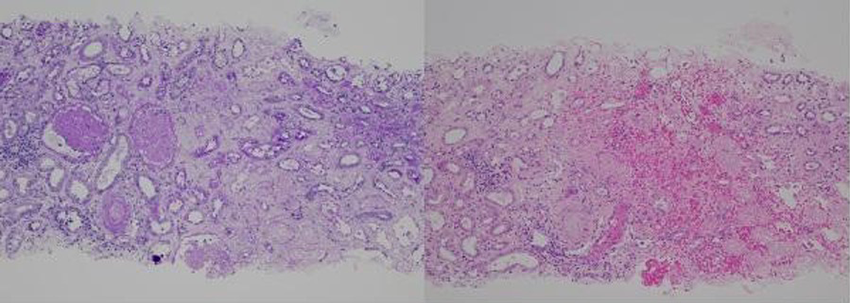

腎生検の弱拡大(左:PAS染色,右:HE染色)を示す。光顕所見として正しいのはどれか。

本症例は急激な腎機能障害を来した中年女性症例で、腎生検で出血性の腎皮質壊死があり、その原因として細小動脈レベルに内膜の浮腫性肥厚による閉塞を認めている。腎の細小動脈に閉塞を来す疾患には、悪性高血圧、結節性多発動脈炎、強皮症腎クリーゼ、薬剤性TMA、コレステリン塞栓症などがあるが、それぞれの血管病変は組織学的に異なった特徴がある。ここではまず、動脈閉塞によって引き起こされる腎皮質壊死の病理所見を確認する。光顕弱拡大では糸球体や尿細管が凝固壊死に陥っており、間質に強い出血を伴っている。炎症細胞浸潤はほとんどなく、急激な経過で起こった出血性梗塞の所見である。急性期では間質は浮腫性であるが、線維化はまだ出現していない。